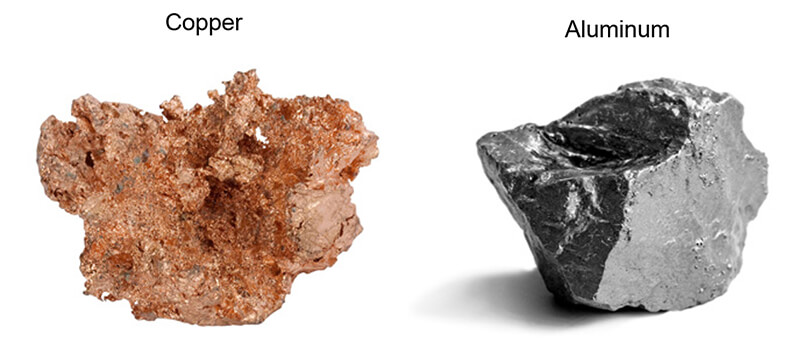

Here we have two examples of conductor metals. Copper and Aluminum. Occasionally these types of metals are used as part of medical implants. Copper may be used in lithium batteries. Devices such as Pacemakers and bladder stimulators may have these lithium batteries. Some of the wires used with pacemakers and stimulators may have copper or other conducting metal alloys as part of the wire. That, combined with the moist tissue inside the body are the perfect combination for transfer of the energy created during a scan.